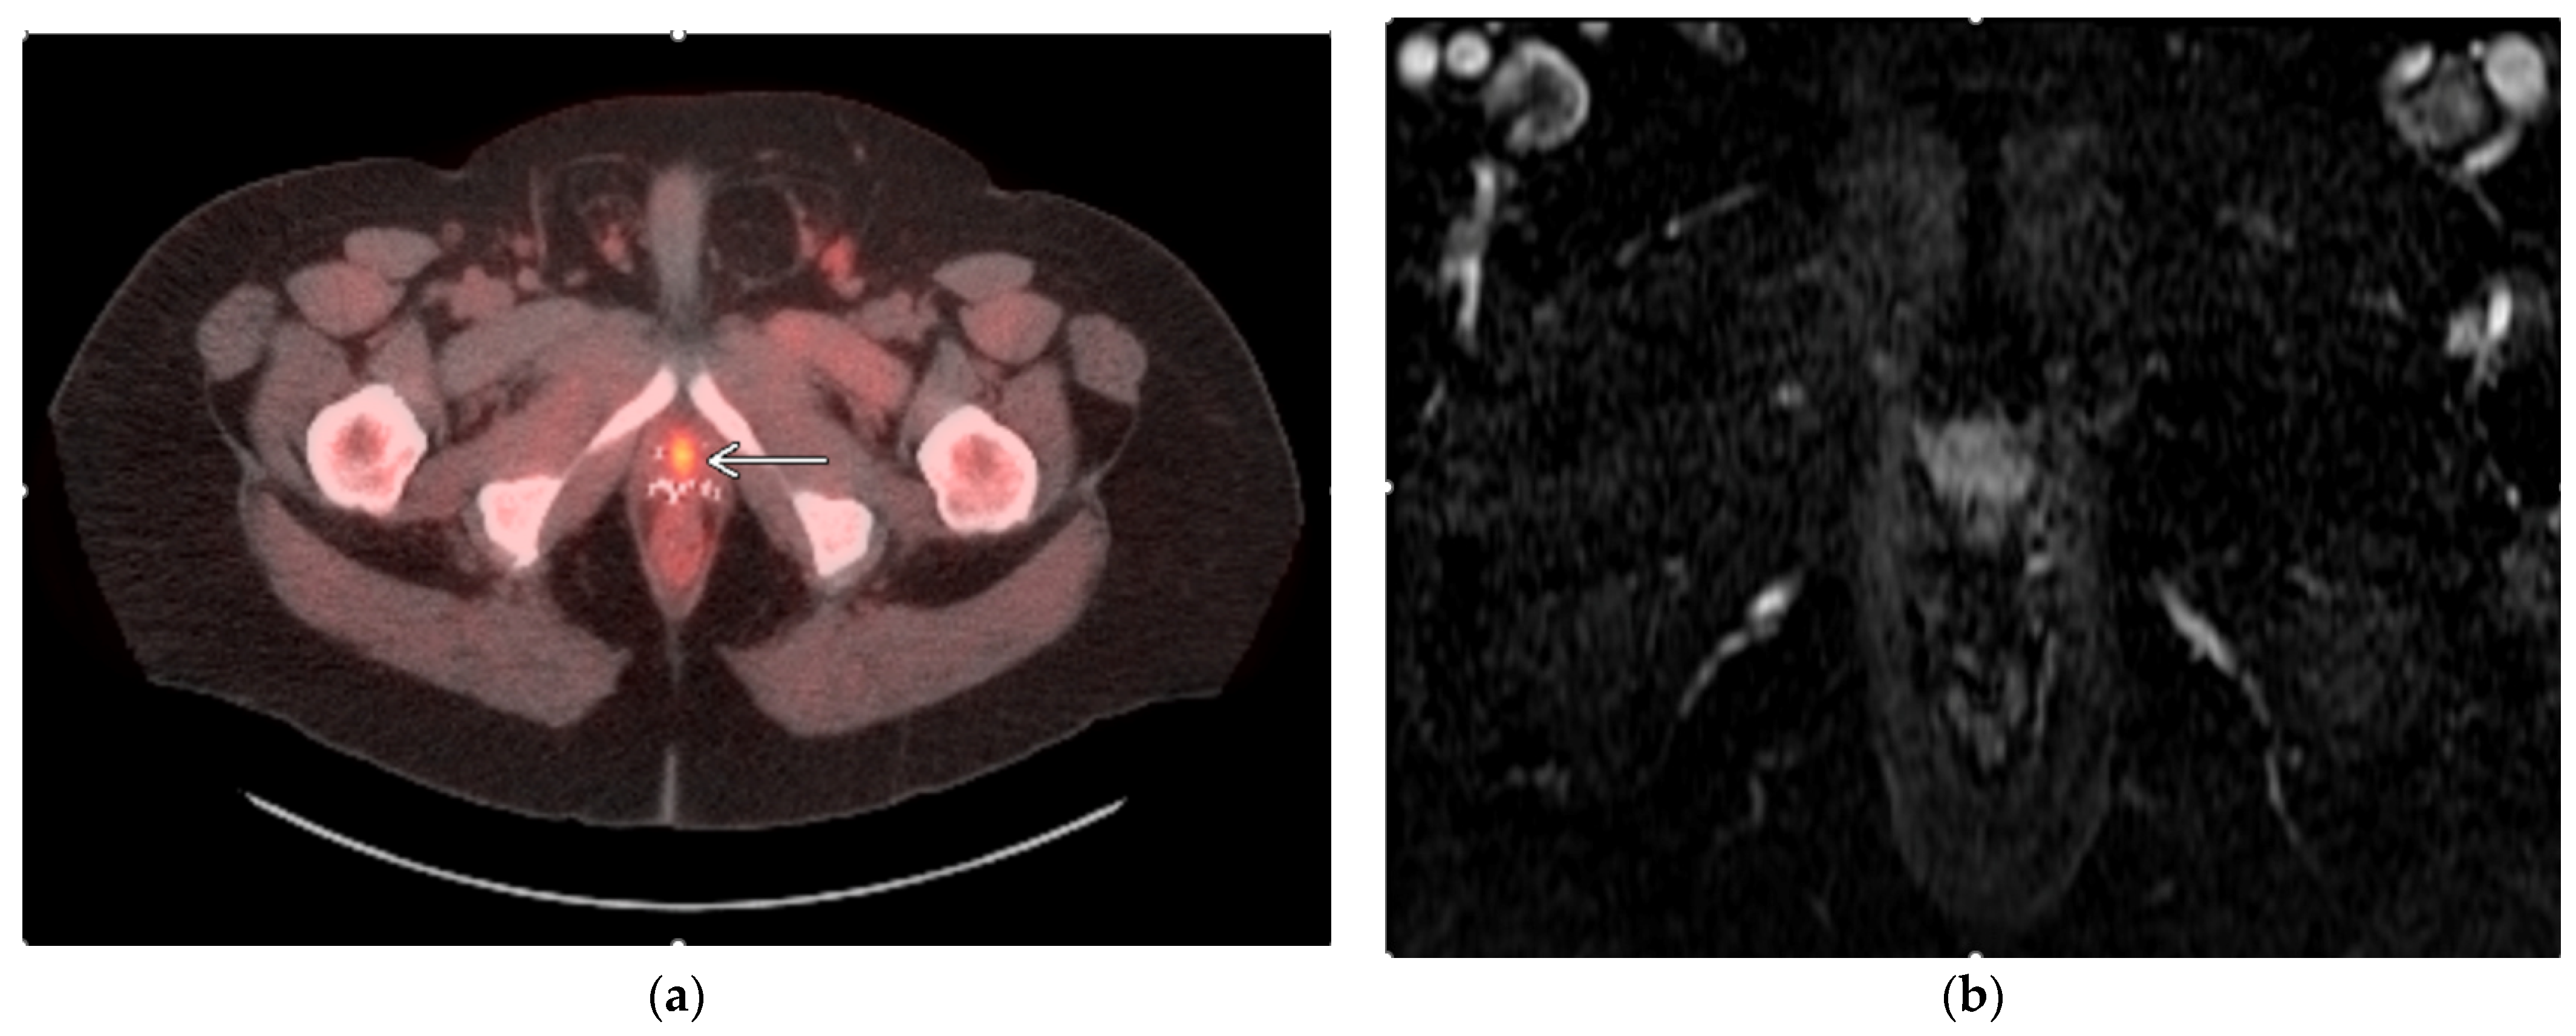

- Gangi, A.; Tsoumakidou, G.; Abdelli, O.; Buy, X.; de Mathelin, M.; Jacqmin, D.; Lang, H. Percutaneous MR-guided cryoablation of prostate cancer: Initial experience. Eur. Radiol. 2012, 22, 1829–1835. [Google Scholar] [CrossRef] [PubMed]

- Bomers, J.G.; Yakar, D.; Overduin, C.G.; Sedelaar, J.P.; Vergunst, H.; Barentsz, J.O.; de Lange, F.; Fütterer, J.J. MR imaging-guided focal cryoablation in patients with recurrent prostate cancer. Radiology 2013, 268, 451–460. [Google Scholar] [CrossRef]